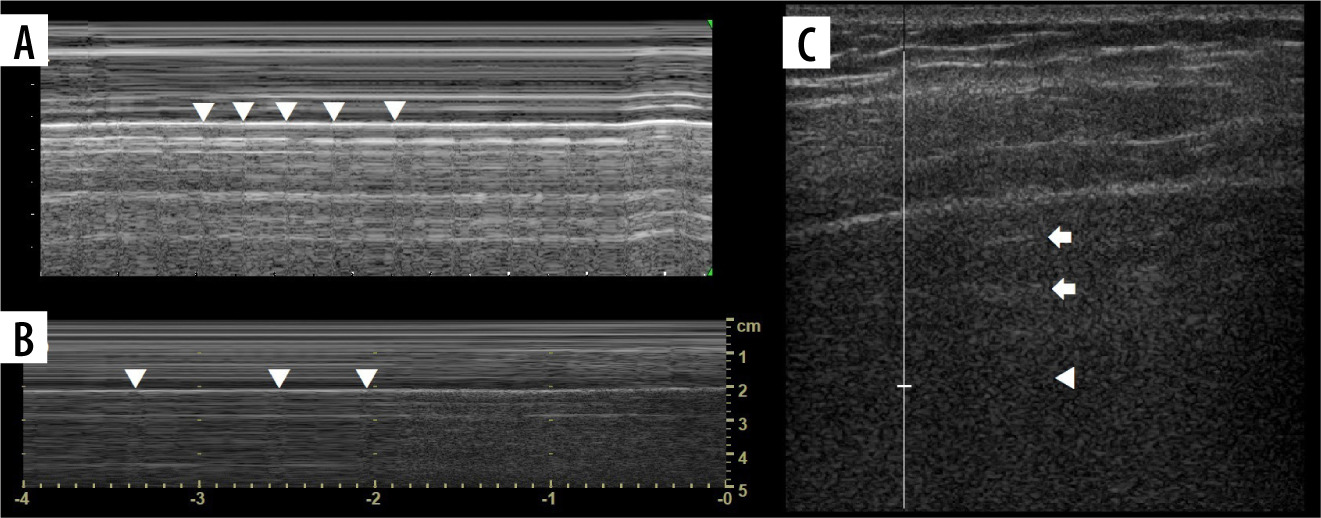

Ultrasound M-mode and B-mode. T- and O-lines, seashore and stratosphere signs (discussed later). A) Physiologic T-lines (white arrowheads) during apnoea on M-mode. There is interspersing seashore and barcode sign. B) Physiologic T-lines (white arrowheads) during apnoea (left, stratosphere sign), not present during breathing (right, seashore sign) presented in M-mode. C) Nearly black ultrasound lung. Note presence of faint A’-lines (white arrows), but not A-line (white arrowhead in expected place)

T-lines

The M-mode images before and after the T-line differ slightly, making the impression of 2 similar pictures glued together at the edges. This “glued” part makes a vertical line of the “T”, and it stops at the pleural line, which makes the horizontal line of the “T”. It is better appreciated if the background granularity of Merlin’s space dynamics is more evident. The circumstance when they might occur in the pneumothorax is explained in the lung point.

Seashore and stratosphere/barcode signs (Figure 7A)

Care must be taken not to confuse muscle sliding (above the pleural line) with lung sliding (below the pleural line). Physiologically there is an end-expiratory pause, which will cause stratosphere sign in healthy subjects (Figure 7B). Sometimes lung sliding is very discrete, making little granularity (sand). Provoking the lung pulse may be useful in such instances. If stratosphere sign is present, sonographic confirmation of pneumothorax requires finding the lung point.

Lung point

Lung point (Figure 7B) may be localised [30], even in unusual locations [31]. In such situations it was proposed that it be called double lung point, but due to the overlap we would advise using the term localised pneumothorax, without the “new” sign. In a supine patient, more lateral (or then, posterior) lung point, indicates greater pneumothorax volume. In pneumothoraces where pleural contact is partially spared, parts of pleurae touch periodically to a greater degree, due to breathing and vibration. This makes it possible to register the lung point on M-mode while staying still. Lung sliding may be discrete at that point (as is probably the case in Figure 8, where we saw no apparent lung sliding on B-mode in the same spot, only on M-mode, repeatedly). This justifies periodic presence of T-lines and lung sliding, sometimes obvious only on M-mode, especially in thin pneumothoraces, like in our case.